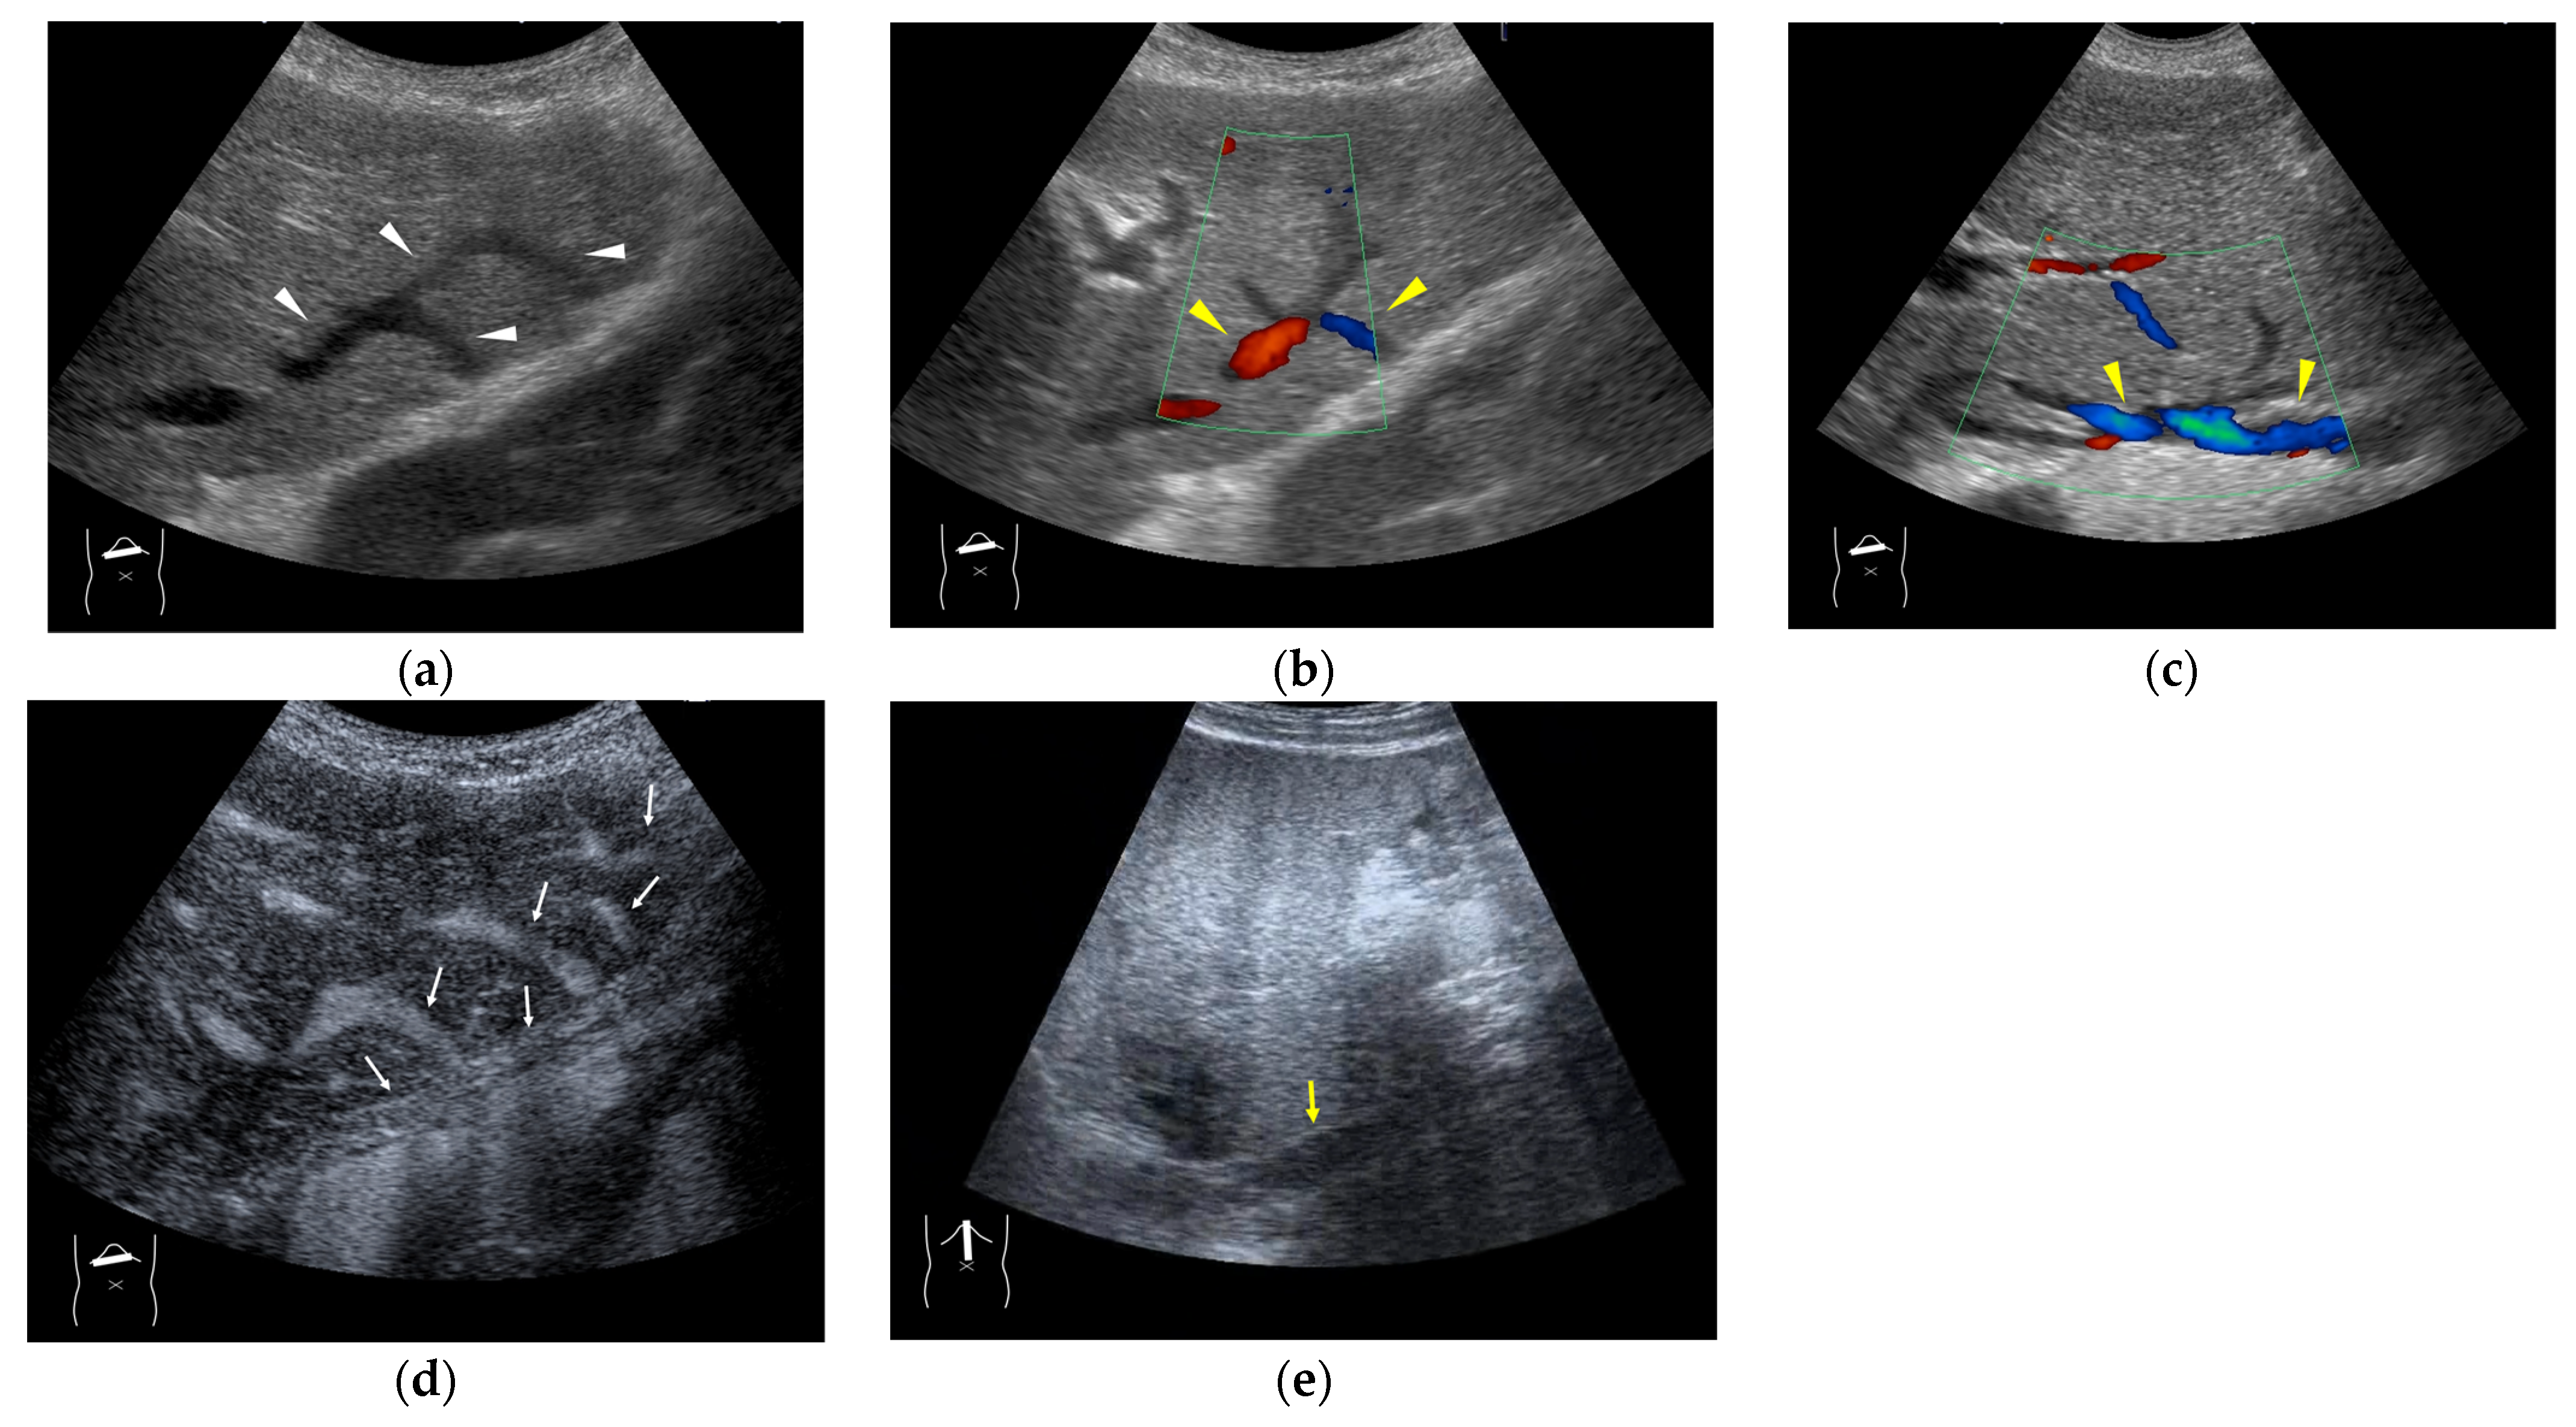

4.2. Congenital P-V Shunts

- Alvi, A.A.; Pichardo, J.; Gupta, S.; Goyal, P.; Mattana, J. An Interesting Case of Congenital Intrahepatic Porto-hepatic Shunt as a Cause of Unexplained Encephalopathy. Cureus 2020, 12, e7639. [Google Scholar] [CrossRef]

- Park, J.H.; Cha, S.H.; Han, J.K.; Han, M.C. Intrahepatic portosystemic venous shunt. AJR Am. J. Roentgenol. 1990, 155, 527–528. [Google Scholar] [CrossRef] [PubMed]